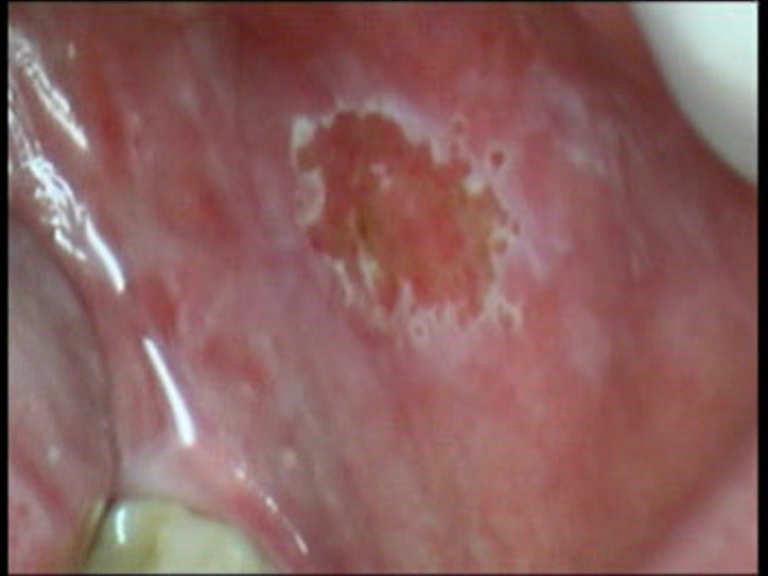

DiodeLaser 810nm

Power: 2.5 Watt, CW

Fibre 400 micron

Er.Cr.:YSGG

Watt: 2,0

Hz: 30